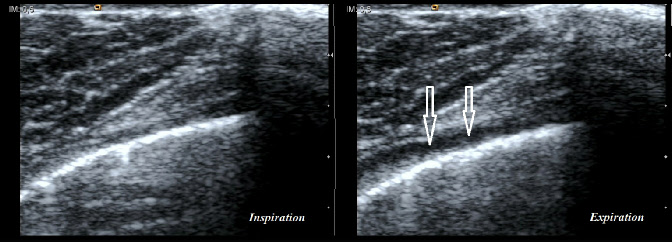

Coupes intercostales d’un épanchement pleural millimétrique lors d’une “ manœuvre de facilitation ”. La première image (image de gauche), en inspiration, rend difficilement visualisable (flèches blanches) la présence d’un liquide qui apparaît à l’expiration forcée (image de droite)